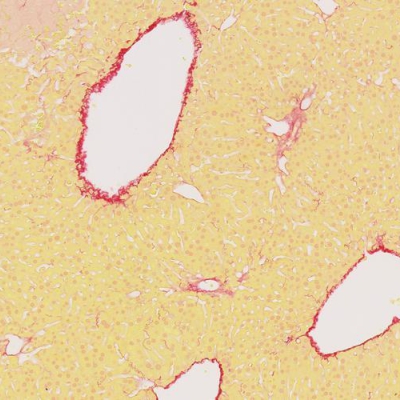

EVG染色(弹力纤维)

¥25元/样

706